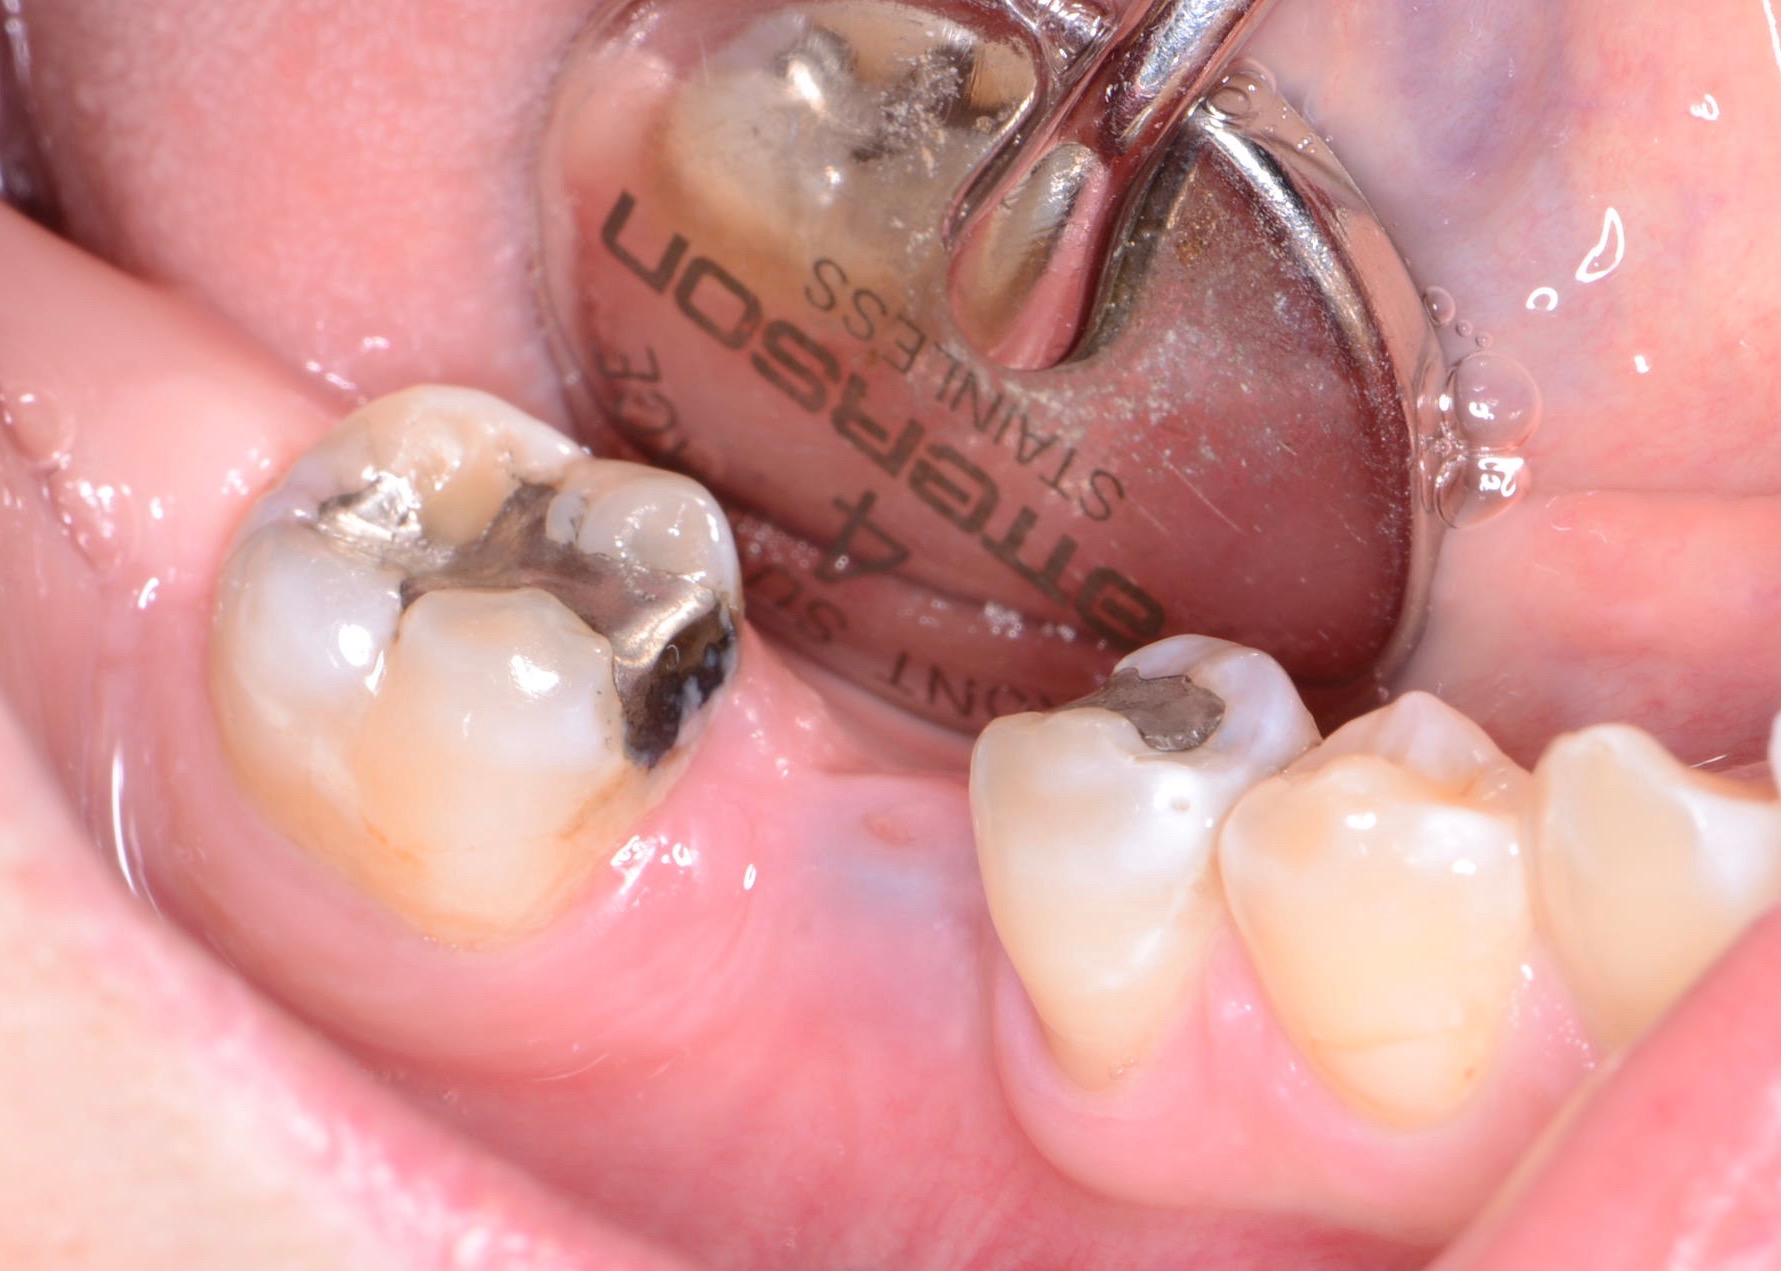

Fig 14. Clear resin cement left on the implant abutment.

Figure 14

Fig 15. Implant abutment following cement removal.

Figure 15

Excess Cement Leading to Peri-implantitis

If all implant-supported crowns could be designed for screw retention, no discussion of excess cement would be necessary. However, screw retention is not always possible depending on the location of the access opening and because of the unesthetic appearance in anterior restorations or the mesial/distal angulation of the implant compromising the path of insertion (Figure 12). Residual cement left after crown cementation on implants can lead to peri-implant inflammation, peri-implantitis, and eventual loss of the implant (Figure 13 through Figure 15).25 The presence of lingering excess cement can encourage the development of bacterial colonization and peri-implantitis. Conversely, when too little cement is used, voids in the cement layer can occur and the prosthesis can become loose.26 The deeper the implant crown margin, the more difficult it is to remove excess cement.27

Radiopaque cements that contain zinc phosphate and zinc oxide (with and without eugenol) should be considered to help identify excess interproximal cement; however, this should be used secondarily to proper margin height and careful removal of cement during cementation. Resin cements lack the same opacity as zinc-containing cements and have been shown to be the most difficult to remove.28 Often in the process of removing this excess cement, the abutment surface becomes scratched and damaged, potentiating further plaque accumulation.29

Several modifications in abutment design and cementation have been suggested. Placing vent holes in the abutment during fabrication or leaving most of the screw-access chamber open for access has reduced the amount of cement that expresses out into the sulcus.26 It is also beneficial to extraorally express excess cement on an abutment replica prior to final crown seating to minimize complications. If retrievability is desired with cementable implant crowns, weaker cements (eg, zinc oxide eugenol) should be used first and progressively changed until the desired retention is achieved.